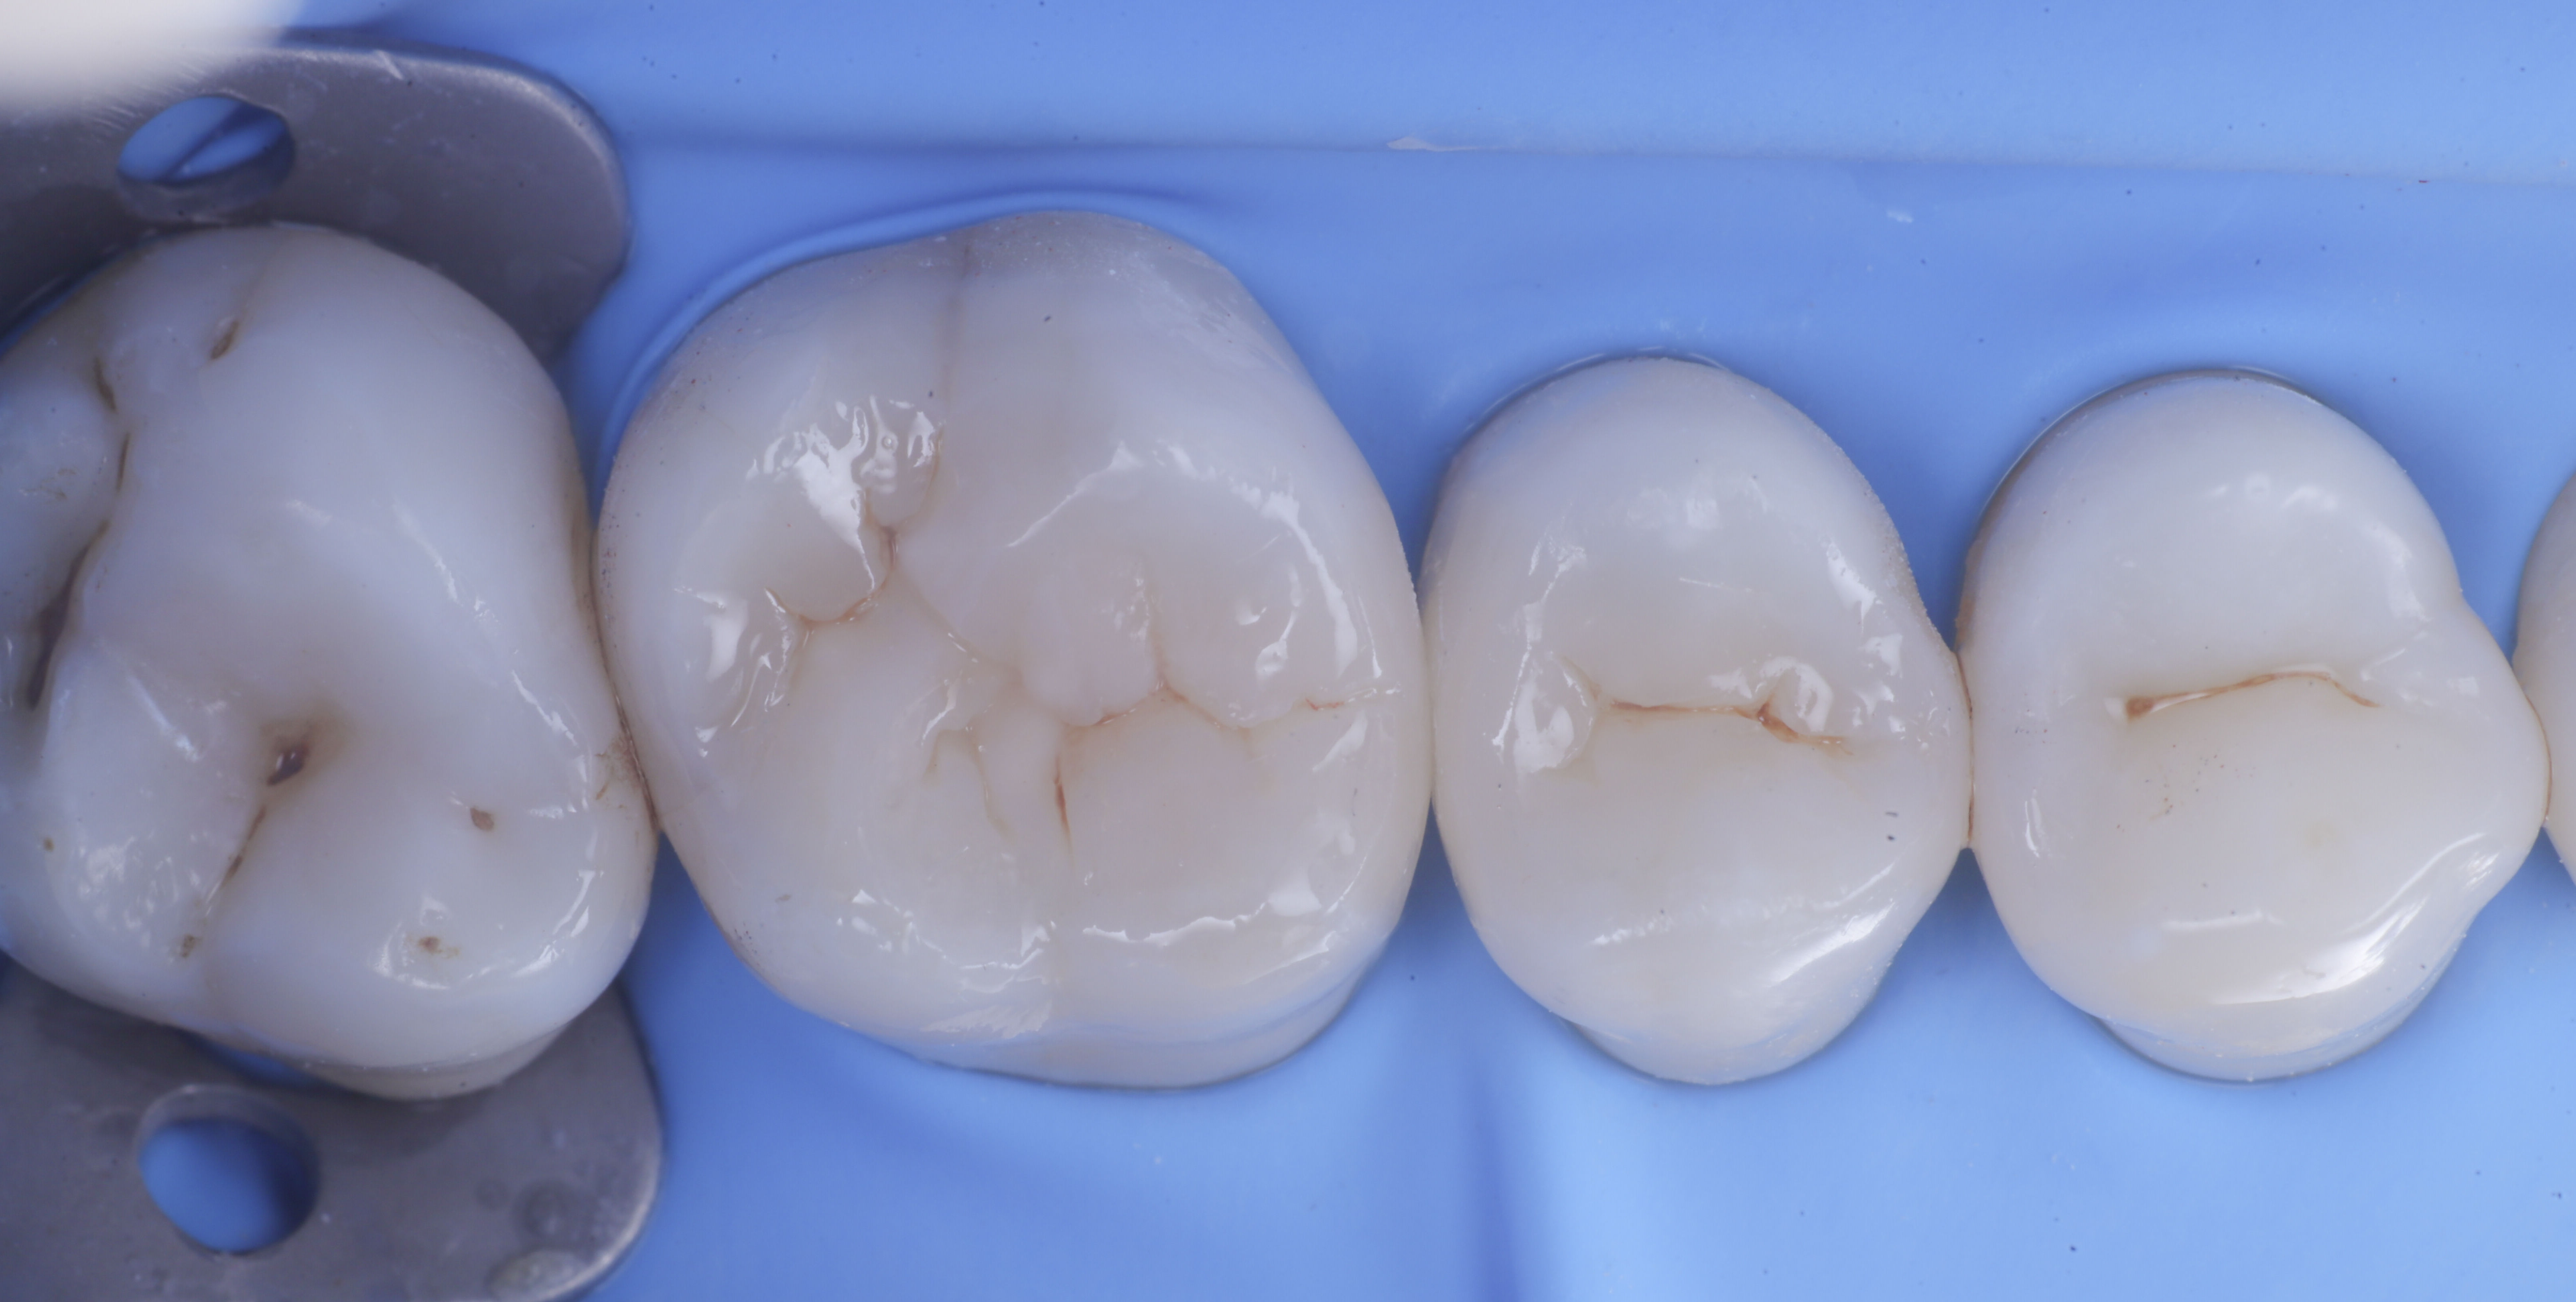

foto 6 Aspetto occlusale delle pareti interprossimali appena create

foto 7 Aspetto vestibolare delle pareti interprossimali appena create

foto 8 Modellazione ed aspetto occlusale